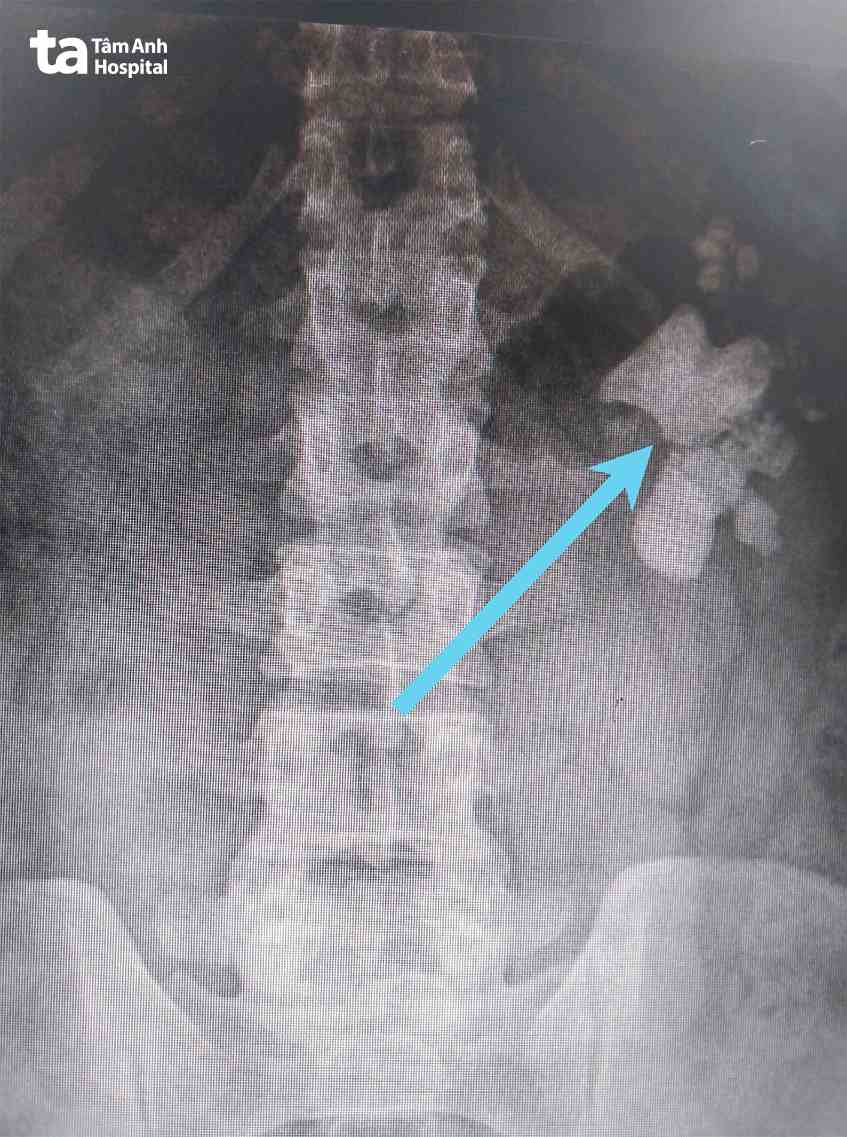

Bác sĩ Hoan cho biết kết quả chụp cắt lớp vi tính (CT) thấy trong bể thận trái của anh T. có rất nhiều sỏi đủ kích thước. Ngoài ra, nồng độ bạch cầu trong nước tiểu tăng là dấu hiệu nhiễm khuẩn đường tiểu nhưng người bệnh chưa có biểu hiện sốt, rét run.

Sau 150 phút, ê kíp mổ lấy hết sỏi trong thận trái người bệnh. Theo quan sát, viên sỏi lớn nhất là sỏi san hô có nhiều nhánh, kích thước 5cm (cỡ quả trứng gà). Khoảng 5-6 viên sỏi kích thước khoảng 1cm và hàng trăm viên sỏi nhỏ hơn với đủ kích thước, hình dạng.